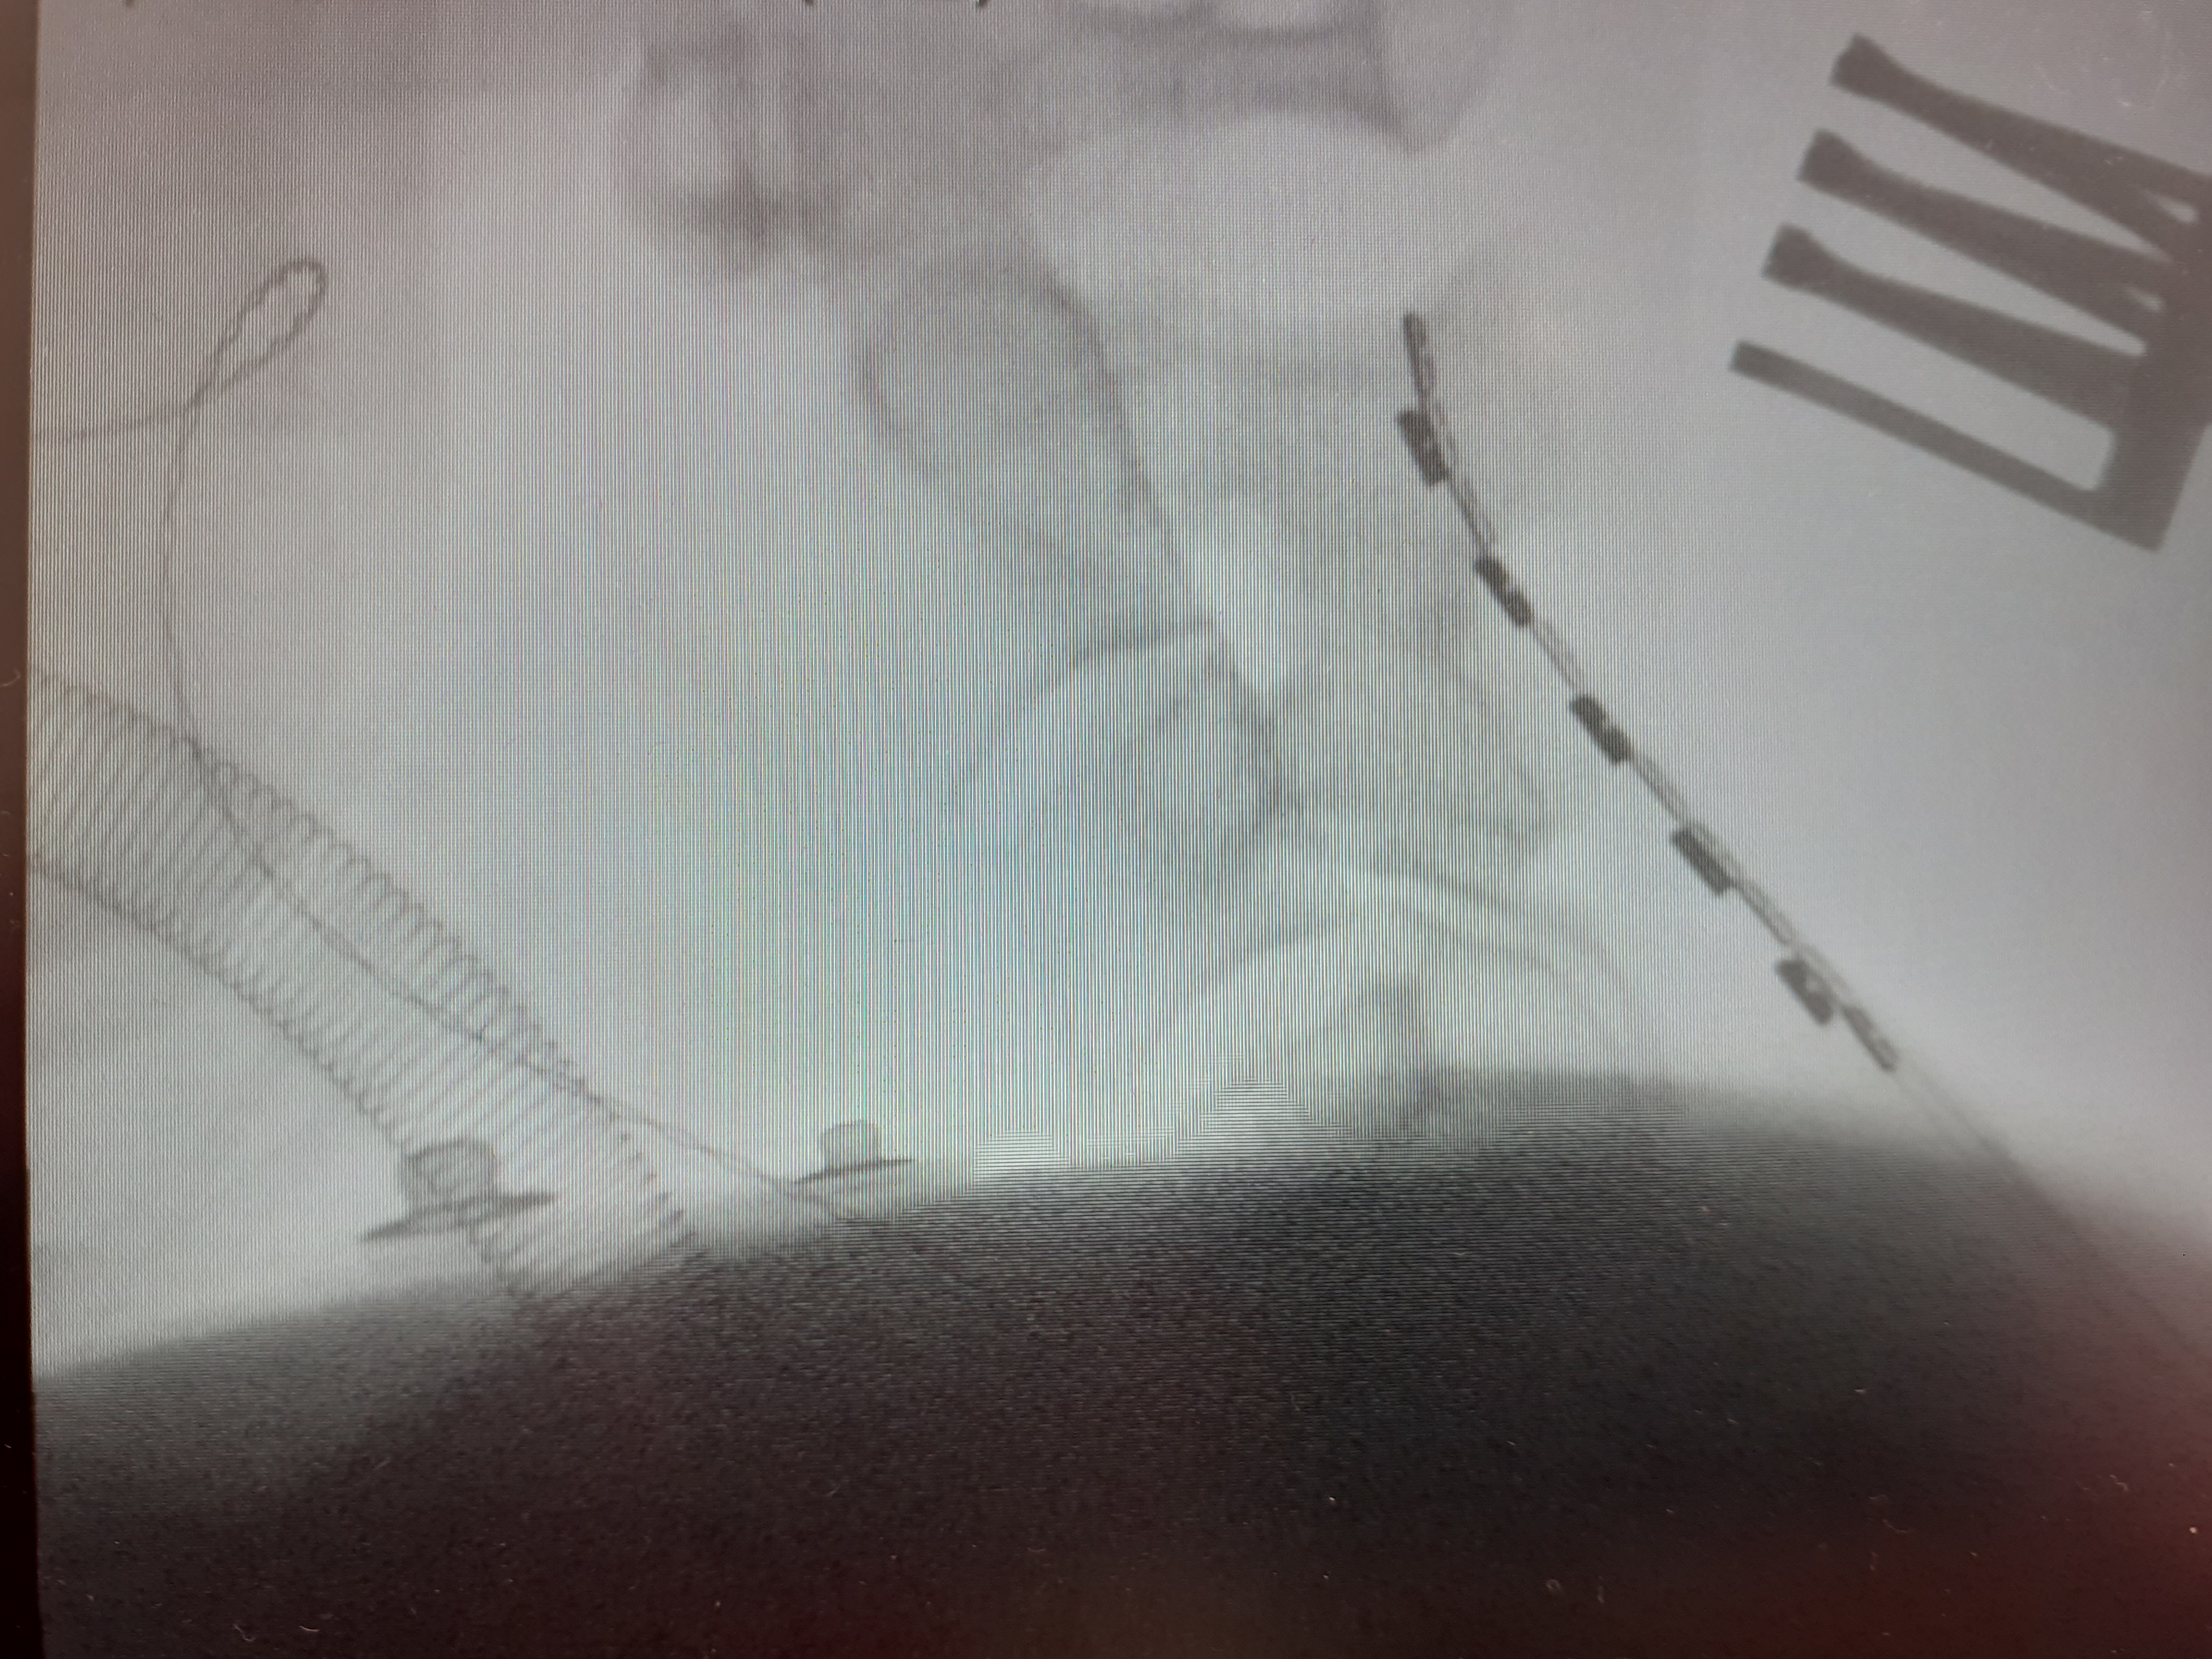

I think I mentioned in my pre-surgery post that I had asked for some pictures of what they were actually doing inside me. I asked again whilst I was at the clinic if the images could be sent over, and I’ve since received them.

The Abbott electrode is not in my mouth as the image suggests, and nor did I have a pair of round glasses on during surgery! Actually, I was unconscious, so who knows if it is a pair of glasses? 😆

The white area next to the electrode in the lateral view is scar tissue that Mr Mundil was worried about removing more than he had because it was extremely hard, and too close to the spinal cord, thus there was risk of damaging the cord. It is unfortunately this scar tissue that is blocking the closed-loop capability as the device needs to receive signals back from the lower end of the paddle to close the loop. They tried sending the input signals to the lower end so that the responses could be picked up from the top where it is close to the cord, but it was not providing any benefit without increasing the power to inappropriate levels.